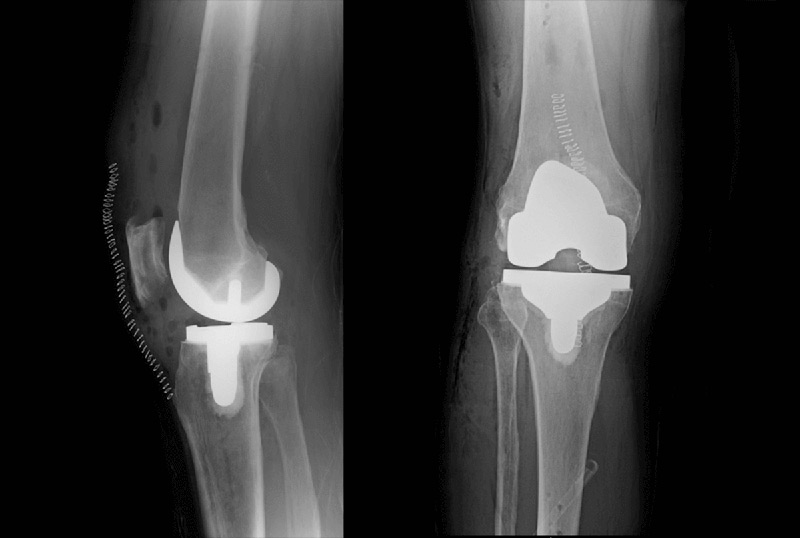

Η τεχνική TKR-MAKOplasty που κάνει χρήση της τεχνολογία του ρομποτικού βραχίονα (MAKO Robotic-Arm Assisted Technology) σε συνδυασμό  με το εμφύτευμα γόνατος Triathlon έχει αλλάξει τον τρόπο με τον οποίο πραγματοποιούνται οι αρθροπλαστικές του γόνατος σήμερα.

Με πάνω από μια δεκαετία κλινικής εμπειρίας, τα εμφυτεύματα Triathlon είναι διαφορετικά από τις παραδοσιακές προθέσεις γόνατος επειδή έχουν σχεδιαστεί για να συνεργάζονται με το σώμα και να υποβοηθούν τη φυσική κυκλική κίνηση του γόνατος.

Μελέτες έχουν δείξει ότι σε σύγκριση με τη συμβατική αρθροπλαστική, η ρομποτικά υποβοηθούμενη ολική αρθροπλαστική του γόνατος (TKR-MAKOplasty) συνδέεται με τη ακριβέστερη  τοποθέτησης και ευθυγράμμιση των εμφυτευμάτων, προσφέρει προστασία στους μαλακούς ιστούς γύρω από την άρθρωση και συμβάλει στην περαιτέρω βελτίωση της πρώιμης λειτουργικής ανάρρωσης και στη μείωση του χρόνου νοσηλείας στο νοσοκομείο.